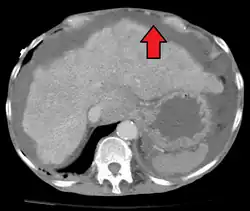

In the developed world, the most common cause is liver cirrhosis.[4] Other causes include cancer, heart failure, tuberculosis, pancreatitis, and blockage of the hepatic vein.[4] In cirrhosis, the underlying mechanism involves high blood pressure in the portal system and dysfunction of blood vessels.[4] Diagnosis is typically based on an examination together with ultrasound or a CT scan.[3] Testing the fluid can help in determining the underlying cause.[3]

Ultrasound investigation is often done before attempts to remove fluid from the abdomen. This may reveal the size and shape of the abdominal organs, and Doppler studies may show the direction of flow in the portal vein, as well as detecting Budd–Chiari syndrome (thrombosis of the hepatic vein) and portal vein thrombosis. The sonographer also can estimate the amount of ascitic fluid, and difficult-to-drain ascites may be drained under ultrasound guidance. An abdominal CT scan is more accurate than a sonogram to reveal abdominal organ structure and morphology.[13]